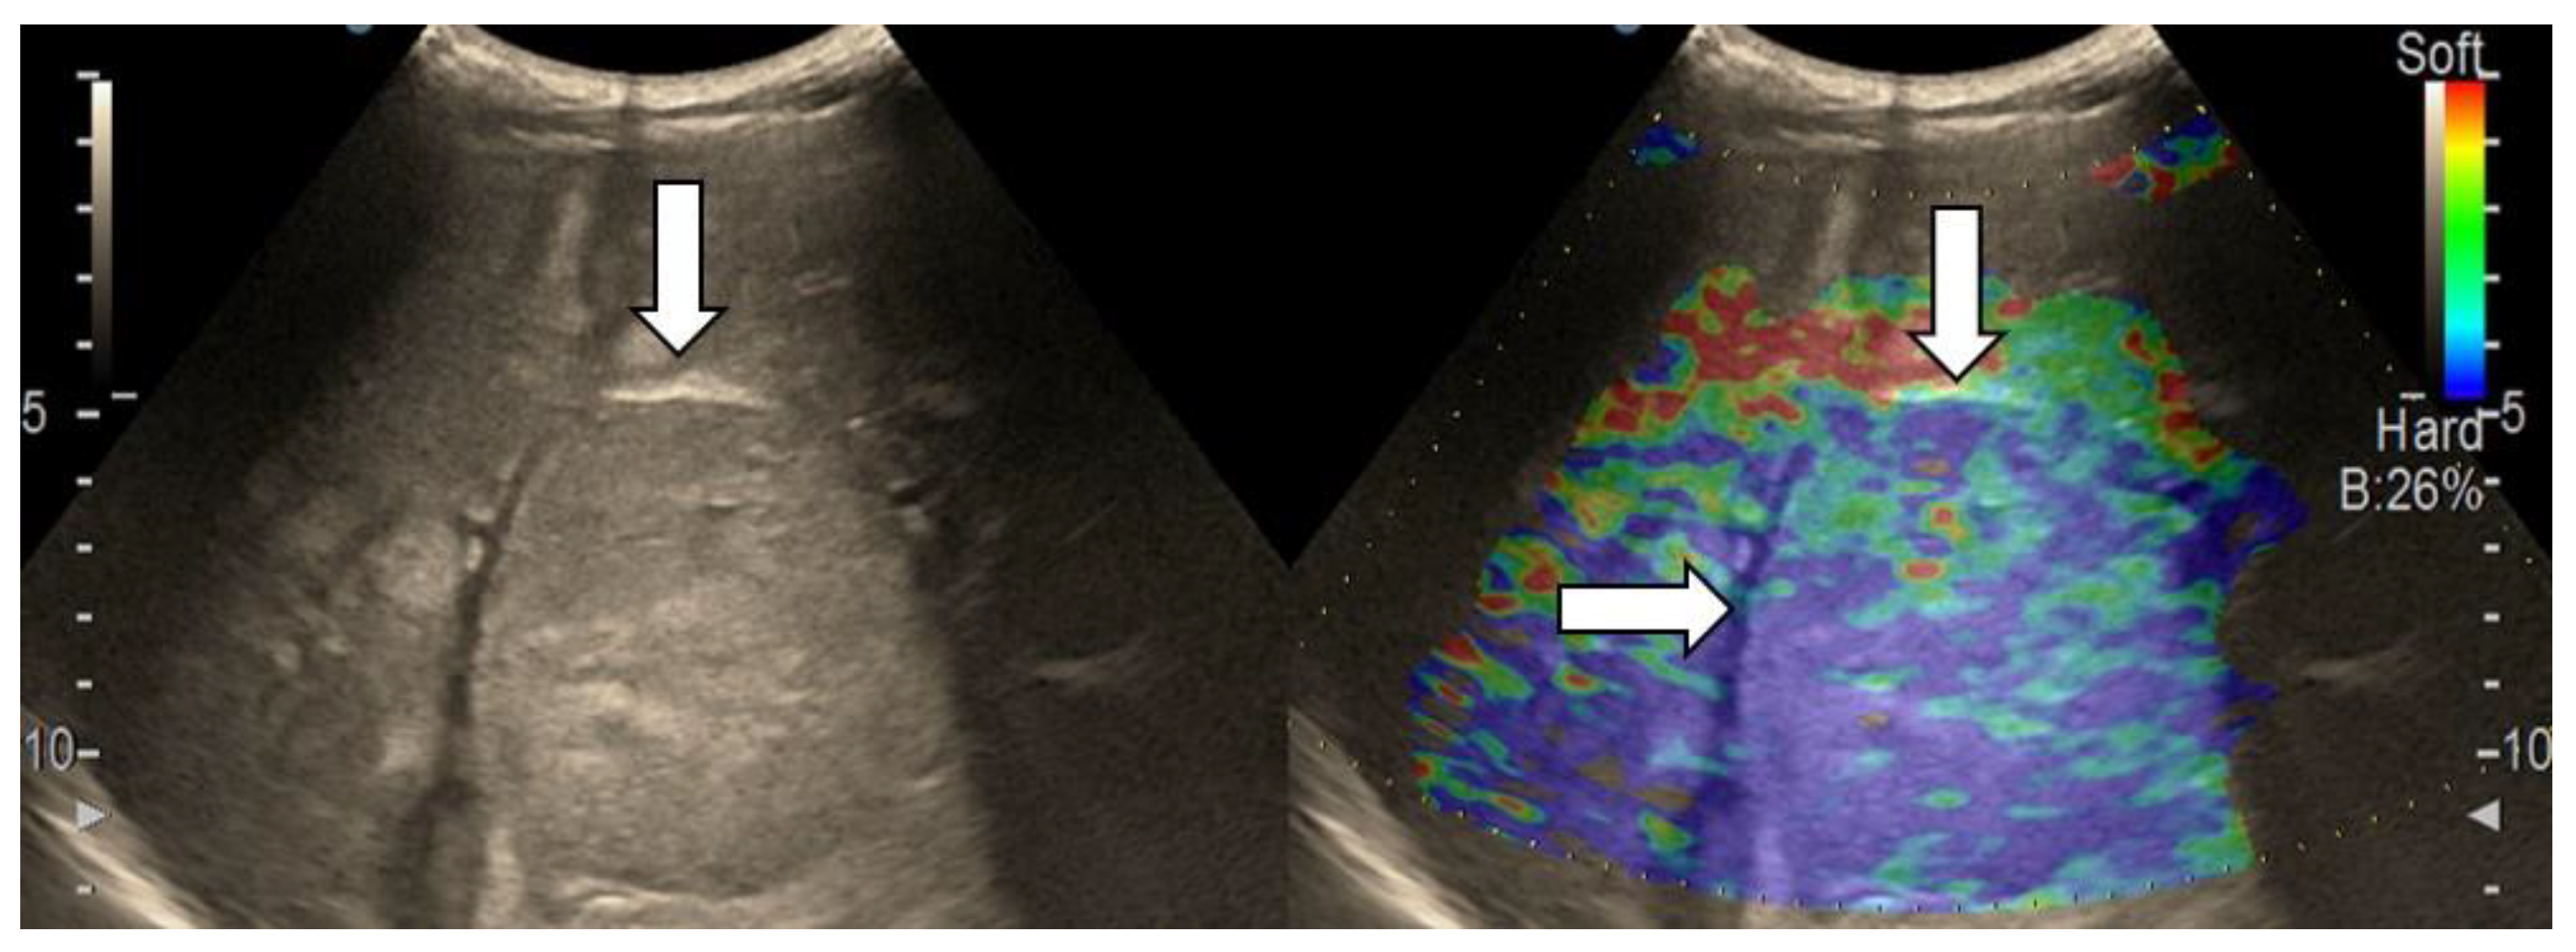

3.4. Real-Time Tissue Elastography

| Elasticity Type | Color Code |

|---|---|

| Type “a” | Homogenously green |

| Type “b” | Mosaic pattern with dominant green areas |

| Type “c” | Mosaic pattern with dominant blue areas |

| Type “d” | Homogenously light blue |

| Type “e” | Homogenously dark blue |

| RTE | Liver Adenoma | HMG | FNH | Complicated Liver Cyst | HCC | iCCA | Liver Metastases | Liver Lymphoma |

|---|---|---|---|---|---|---|---|---|

| Type “a” | 3 | 1 | ||||||

| Type “b” | 1 | 1 | 10 | 3 | 1 | |||

| Type “c” | 1 | 24 | 3 | 6 | ||||

| Type “d” | 1 | |||||||

| Type “e” | 5 | 3 | 1 |